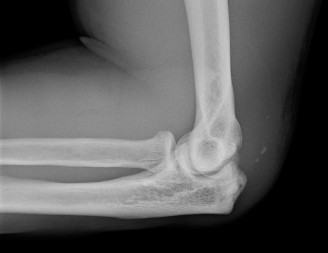

Imaging should include x-rays, which may demonstrate posterior glenoid bone loss or an impaction fracture on the anterior-superior humeral head (Fig. 2–38). CT images with 3D reconstructions can be very useful when assessing the extent of glenoid bone loss and evaluating glenoid and humeral version. Normal glenoid version is from −2 to −8 degrees of retroversion, and this may be increased in posterior instability. MRI can also be useful when assessing the posterior labrum (Fig. 2–39).

Figure 2–38 Radiographs showing a posterior shoulder dislocation.